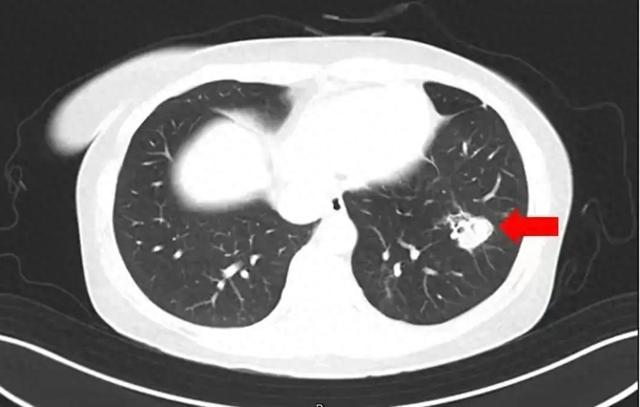

醫生通過問診了解到,沈女士在整理衣櫃時發現裡面長了霉斑,於是對衣櫃做了清理,但清理時沒戴口罩。為進一步確診病情,醫生為沈女士進行纖維支氣管鏡檢查及肺泡灌洗液病原體檢測,果然發現氣道壁上有大量白色菌斑,化驗後確認是曲霉菌。